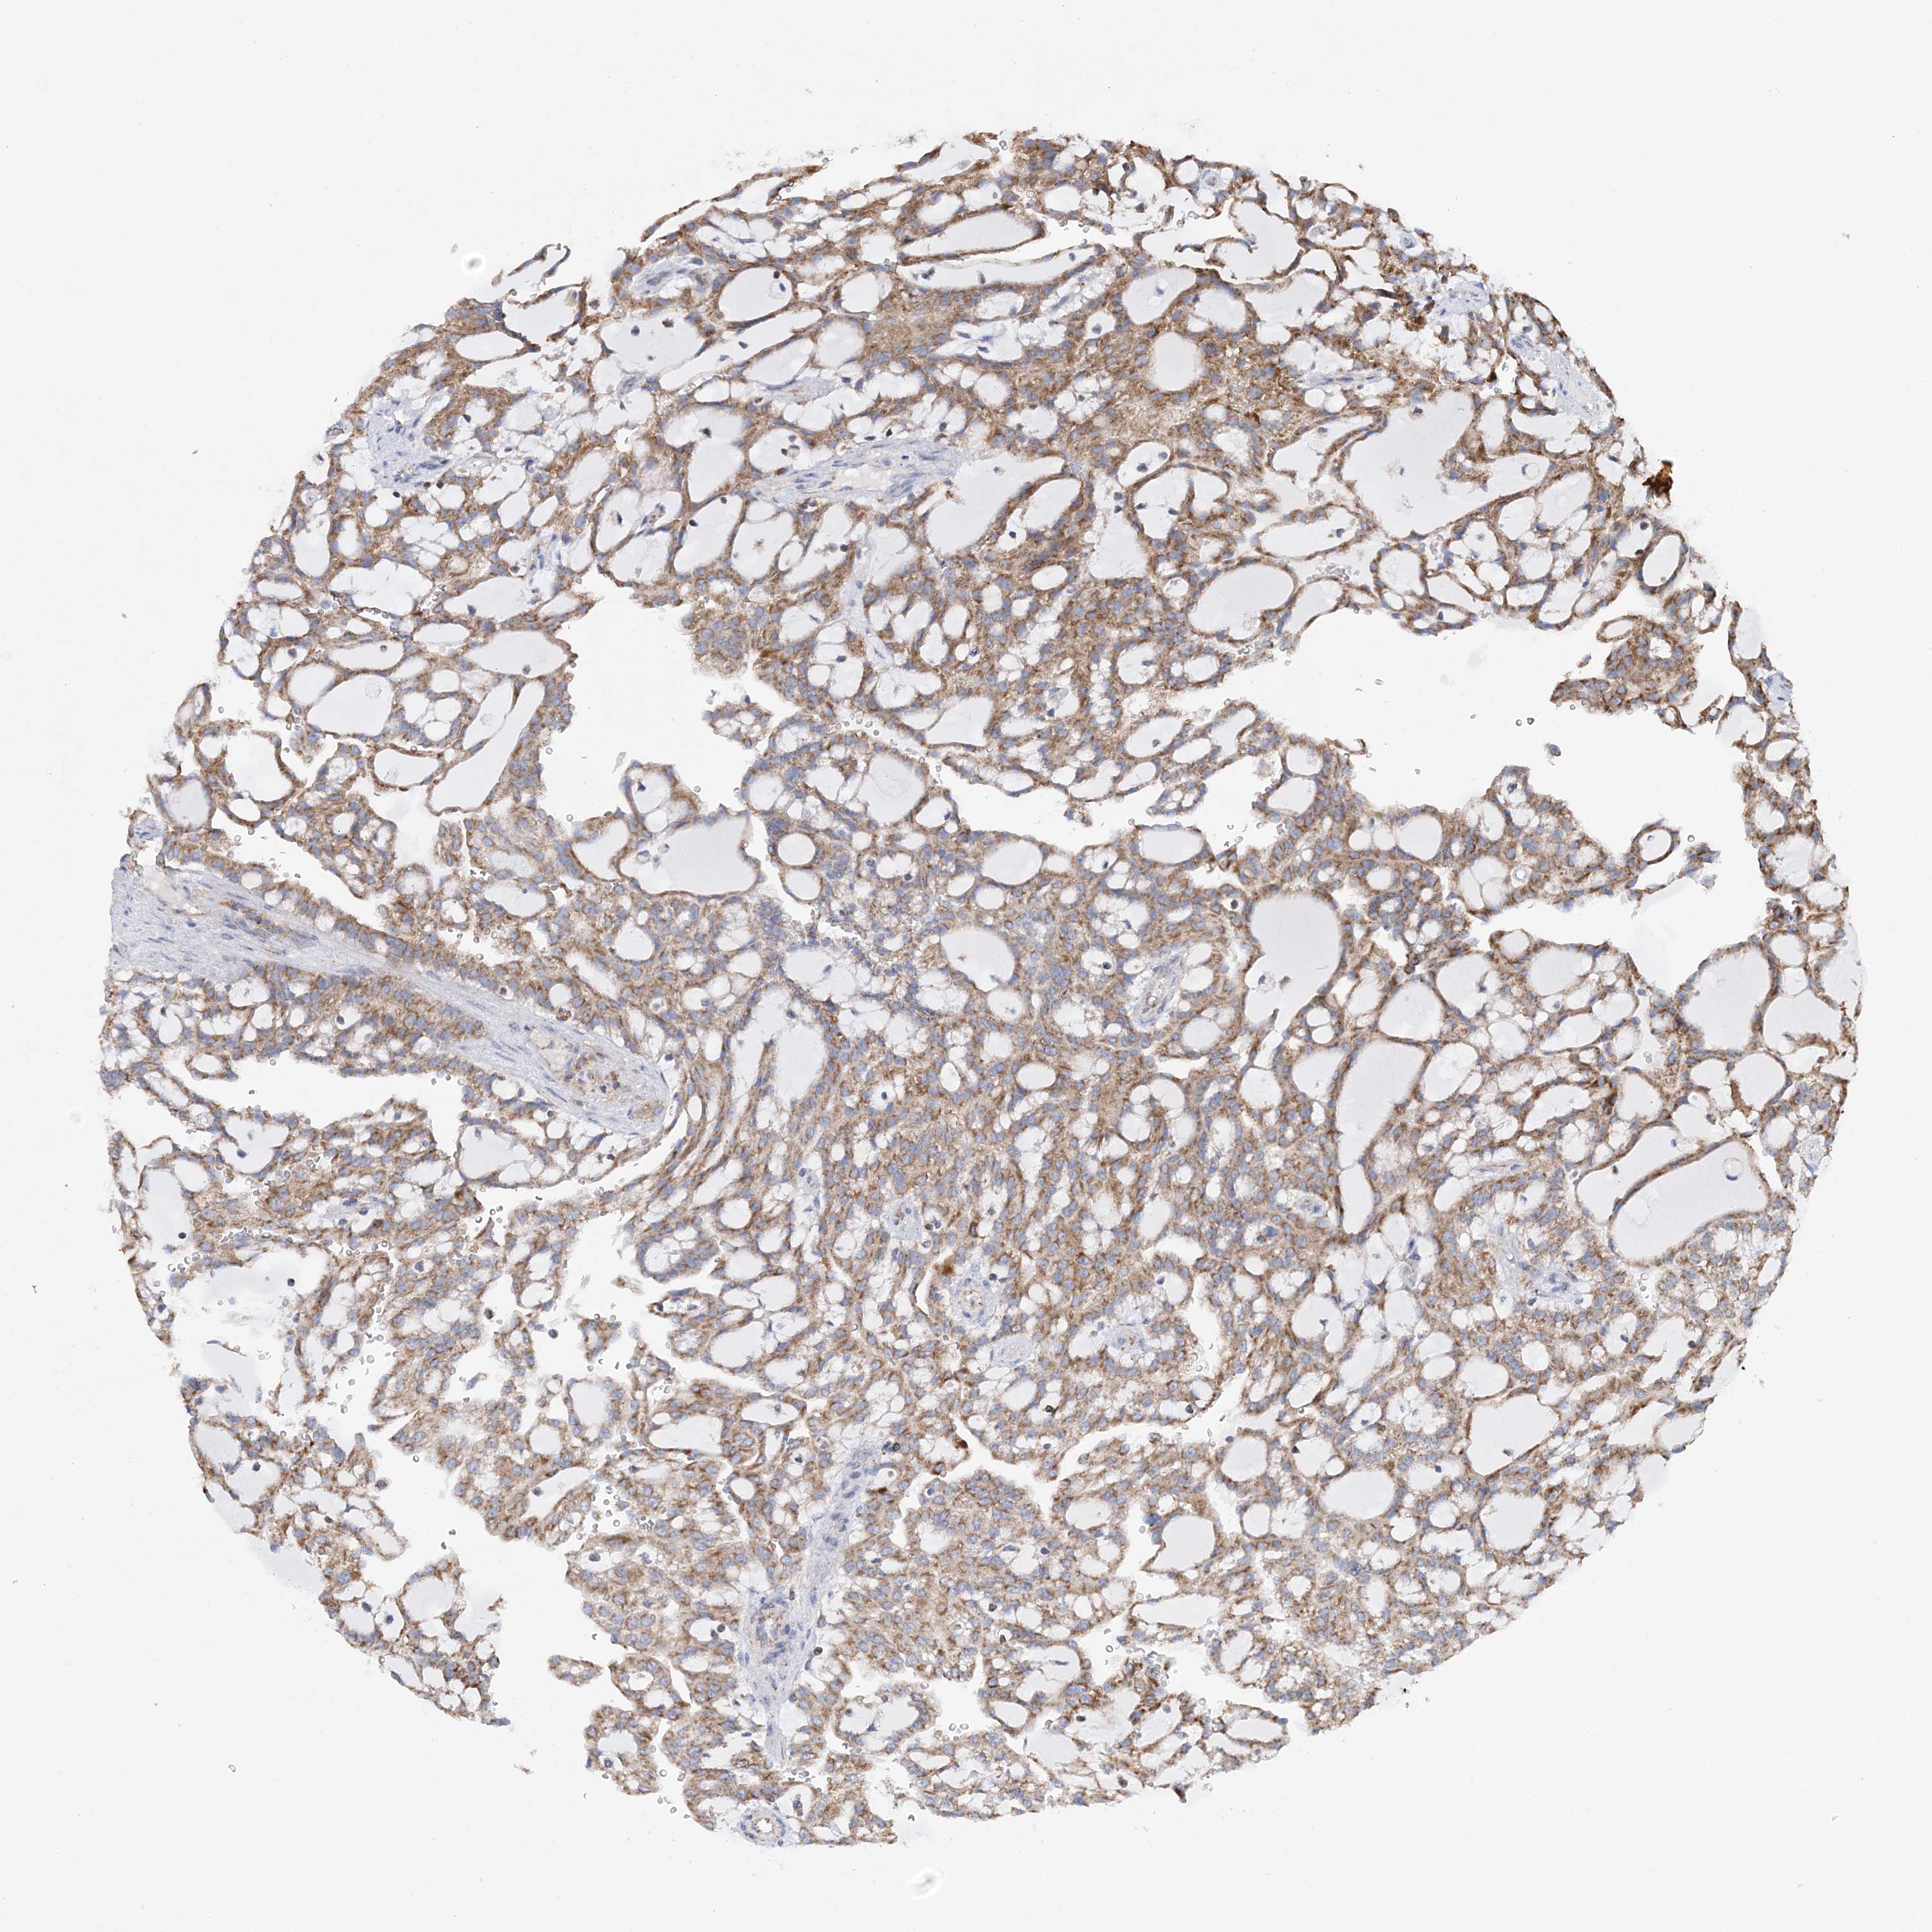

KIDNEY RENAL CLEAR CELL CARCINOMA (VALIDATION) - Interactive survival scatter ploti

The Survival Scatter plot shows the clinical status (i.e. dead or alive) for all individuals in the patient cohort, based on the same data that underlies the corresponding Kaplan-Meier plots. Patients that are alive at last time for follow-up are shown in blue and patients who have died during the study are shown in red.

The x-axis shows the expression levels (FPKM) of the investigated gene in the tumor tissue at the time of diagnosis. The y-axis shows the follow-up time after diagnosis (years). Both axes are complimented with kernel density curves demonstrating the data density over the axes. The top density plot shows the expression levels (FPKM) distribution among dead (red) and alive patients (blue). The right density plot shows the data density of the survived years of dead patients with high and low expression levels respectively, stratified using the cutoff indicated by the vertical dashed line through the Survival Scatter plot. This cutoff is automatically defined based on the FPKM cutoff that minimizes the p-score. The cutoff can be changed by dragging the vertical line or by entering a cutoff value in the square labeled "Current cut-off".

Under the Survival Scatter plot the p-score landscape (black curve; left axis) is shown together with dead median separation (red curve; right axis). Dead median separation is the difference in median mRNA expression between patients who have died with high and low expression, respectively. It is calculated as follows: median FPKM expression of dead patients with high expression - median FPKM expression of dead patients with low expression. This is intended to aid the user in visually exploring custom cutoffs and the associated p-scores and dead median separation.

Individual patient data is displayed and can be filtered by clicking on one or more of the category buttons on the top of the page. Categories describing expression level and patient information include: high, low, alive, dead, female, male and tumor stages. The scale of the x-axis can be toggled between linear and log-scale by clicking on the "x log" button. Mouse-over function shows TCGA ID, patient information and mRNA expression (FPKM) for each patient.

& Survival analysisi

Kaplan-Meier plots summarize results from analysis of correlation between mRNA expression level and patient survival. Patients were divided based on level of expression into one of the two groups "low" (under cut off) or "high" (over cut off). X-axis shows time for survival (years) and y-axis shows the probability of survival, where 1.0 corresponds to 100 percent.

TTC32 is not prognostic in Kidney Renal Clear Cell Carcinoma (validation)

Best expression cut offi

Based on the FPKM value of each gene, patients were classified into two groups and association between prognosis (survival) and gene expression (FPKM) was examined. The best expression cut-off refers the FPKM value that yields maximal difference with regard to survival between the two groups at the lowest log-rank P-value. Best expression cut-off was selected based on survival analysis .

When clicking on this number, the vertical dashed line indicating cut-off, the interactive survival plot, and the Kaplan-Meier curve will be adjusted to show results based on the best expression cut-off.

: 12.8

Median expressioni

Median expression refers to the median FPKM value calculated based on the gene expression (FPKM) data from all patients in this dataset. When clicking on this number, the vertical dashed line indicating cut-off, the interactive survival plot, and the Kaplan-Meier curve will be adjusted to show results based on the median expression.

: N/A

Median follow up timei

Median follow up time refers to the median time (years) after diagnosis with this type of cancer, based on clinical data from all patients in this dataset.

P scorei

Log-rank P value for Kaplan-Meier plot showing results from analysis of correlation between mRNA expression level and patient survival.

N/A

5-year survival highi

5-year survival for patients with higher expression than the expression cutoff.

For melanoma and glioma, 3-year survival is shown.

5-year survival lowi

5-year survival for patients with lower expression than the expression cutoff.

TCGA RNA samplesi

RNA-seq data is reported as average FPKM (number Fragments Per Kilobase of exon per Million reads), generated by the The Cancer Genome Atlas (TCGA) .

Normal distribution across the dataset is visualized with box plots, shown as median and 25th and 75th percentiles. Points are displayed as outliers if they are above or below 1.5 times the interquartile range. FPKM values of the individual samples are presented next to the box plot.

Average pTPM 17.6

Number of samples 100